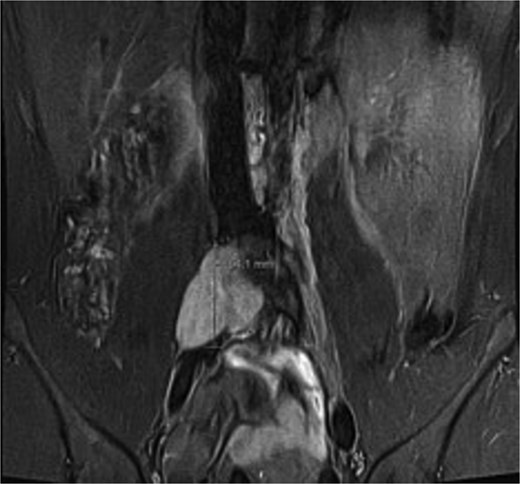

A male in their early twenties presented with a 4-year history of a multitude of symptoms including bone and joint pains in his chest, abdomen and lesser right hip pain. He was seen by an osteopathy and physiotherapist and then referred to a GP who performed plain x-rays of bilateral hips and an abdominal ultrasound, which were normal. His symptoms persisted, and back MRI showed a lobulated mass in the right paraspinal region extending from the L4-L5 to the L5-S1 level, medial to the psoas muscle (Fig. 1), displacing the iliac vessels anteriorly and psoas laterally without involvement of exiting nerves or lumbar plexus (Fig. 2).

Coronal short TI inversion recovery (STIR) showing hypointense lobulated lesion from L4-L5 to L5-S1 level, medial to the right psoas muscle.

Ganglioneuroma was the principal differential. Bloods results were reassuring against a malignant neuroblastic, mixed germ cell tumour or lymphoma. MRI demonstrated common features suggestive but not exclusive to ganglioneuroma including T1 hypointensity and T2 hyperintensity, and mild contrast enhancement [5] (Figs 1 and 2). Differentials included a nerve sheath tumour however there was no definitive associated exiting nerve or lumbar plexus involvement on MRI. Minimal glucose avidity on PET also pointed towards a benign process. The histopathological findings of mature ganglion cells mixed with Schwan cells are the hallmark of ganglioneuroma and important for distinguishing this benign tumour from neural crest derived tumours [8].